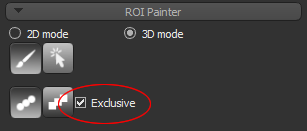

To edit a segmentation, you can automatically re-assign labeled voxels from one region to interest to another with the Brush tools (see Working with the ROI Painter Tools in 2D Views). In addition, when you work in the Exclusive mode with the Brush tools, only the labeled voxels belonging to the selected regions of interest will be affected when painting.

- Select the Exclusive option, circled below.

NOTE In this mode, painting will only be applied to the labeled voxels of the selected regions of interest. Unlabeled voxels will not be painted.